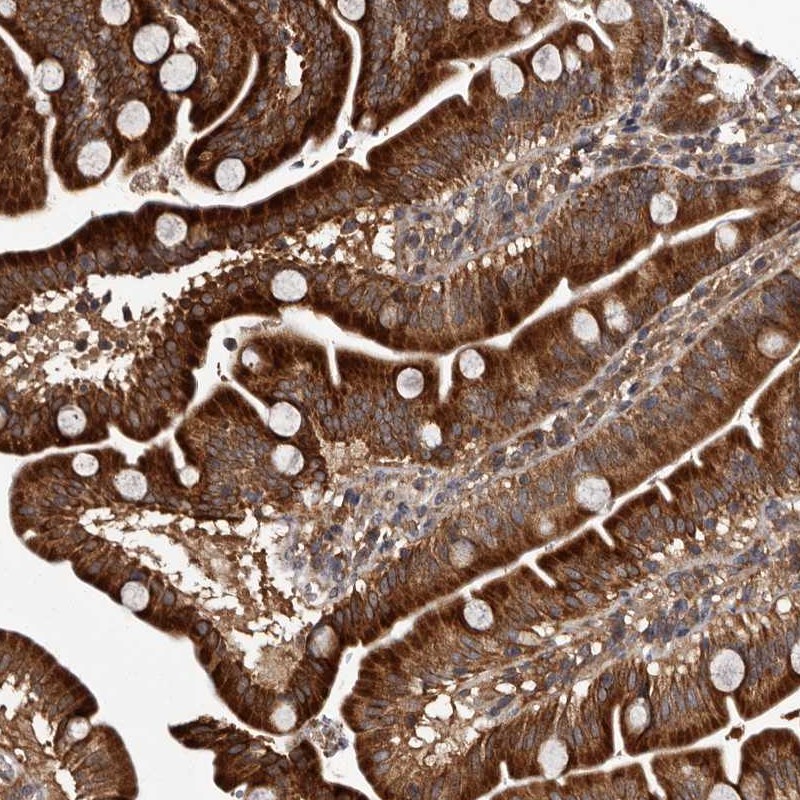

Immunohistochemical staining of human duodenum shows strong cytoplasmic positivity in glandular cells.